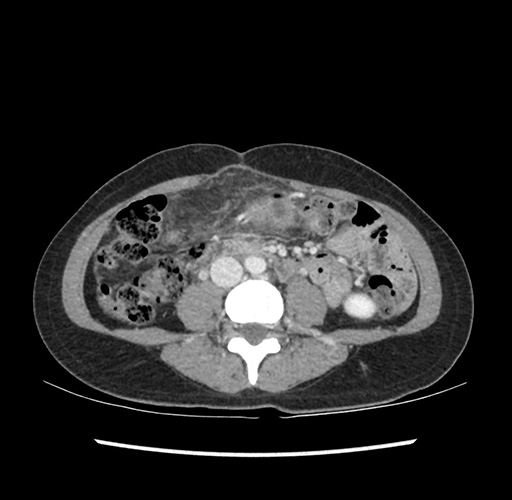

Imaging Analysis

Look through the patient's CT scan to identify any areas of concern for the necessary procedure.

Based on your CT findings, which issue(s) would give reason for "planned slowing down moment(s)" in this case?